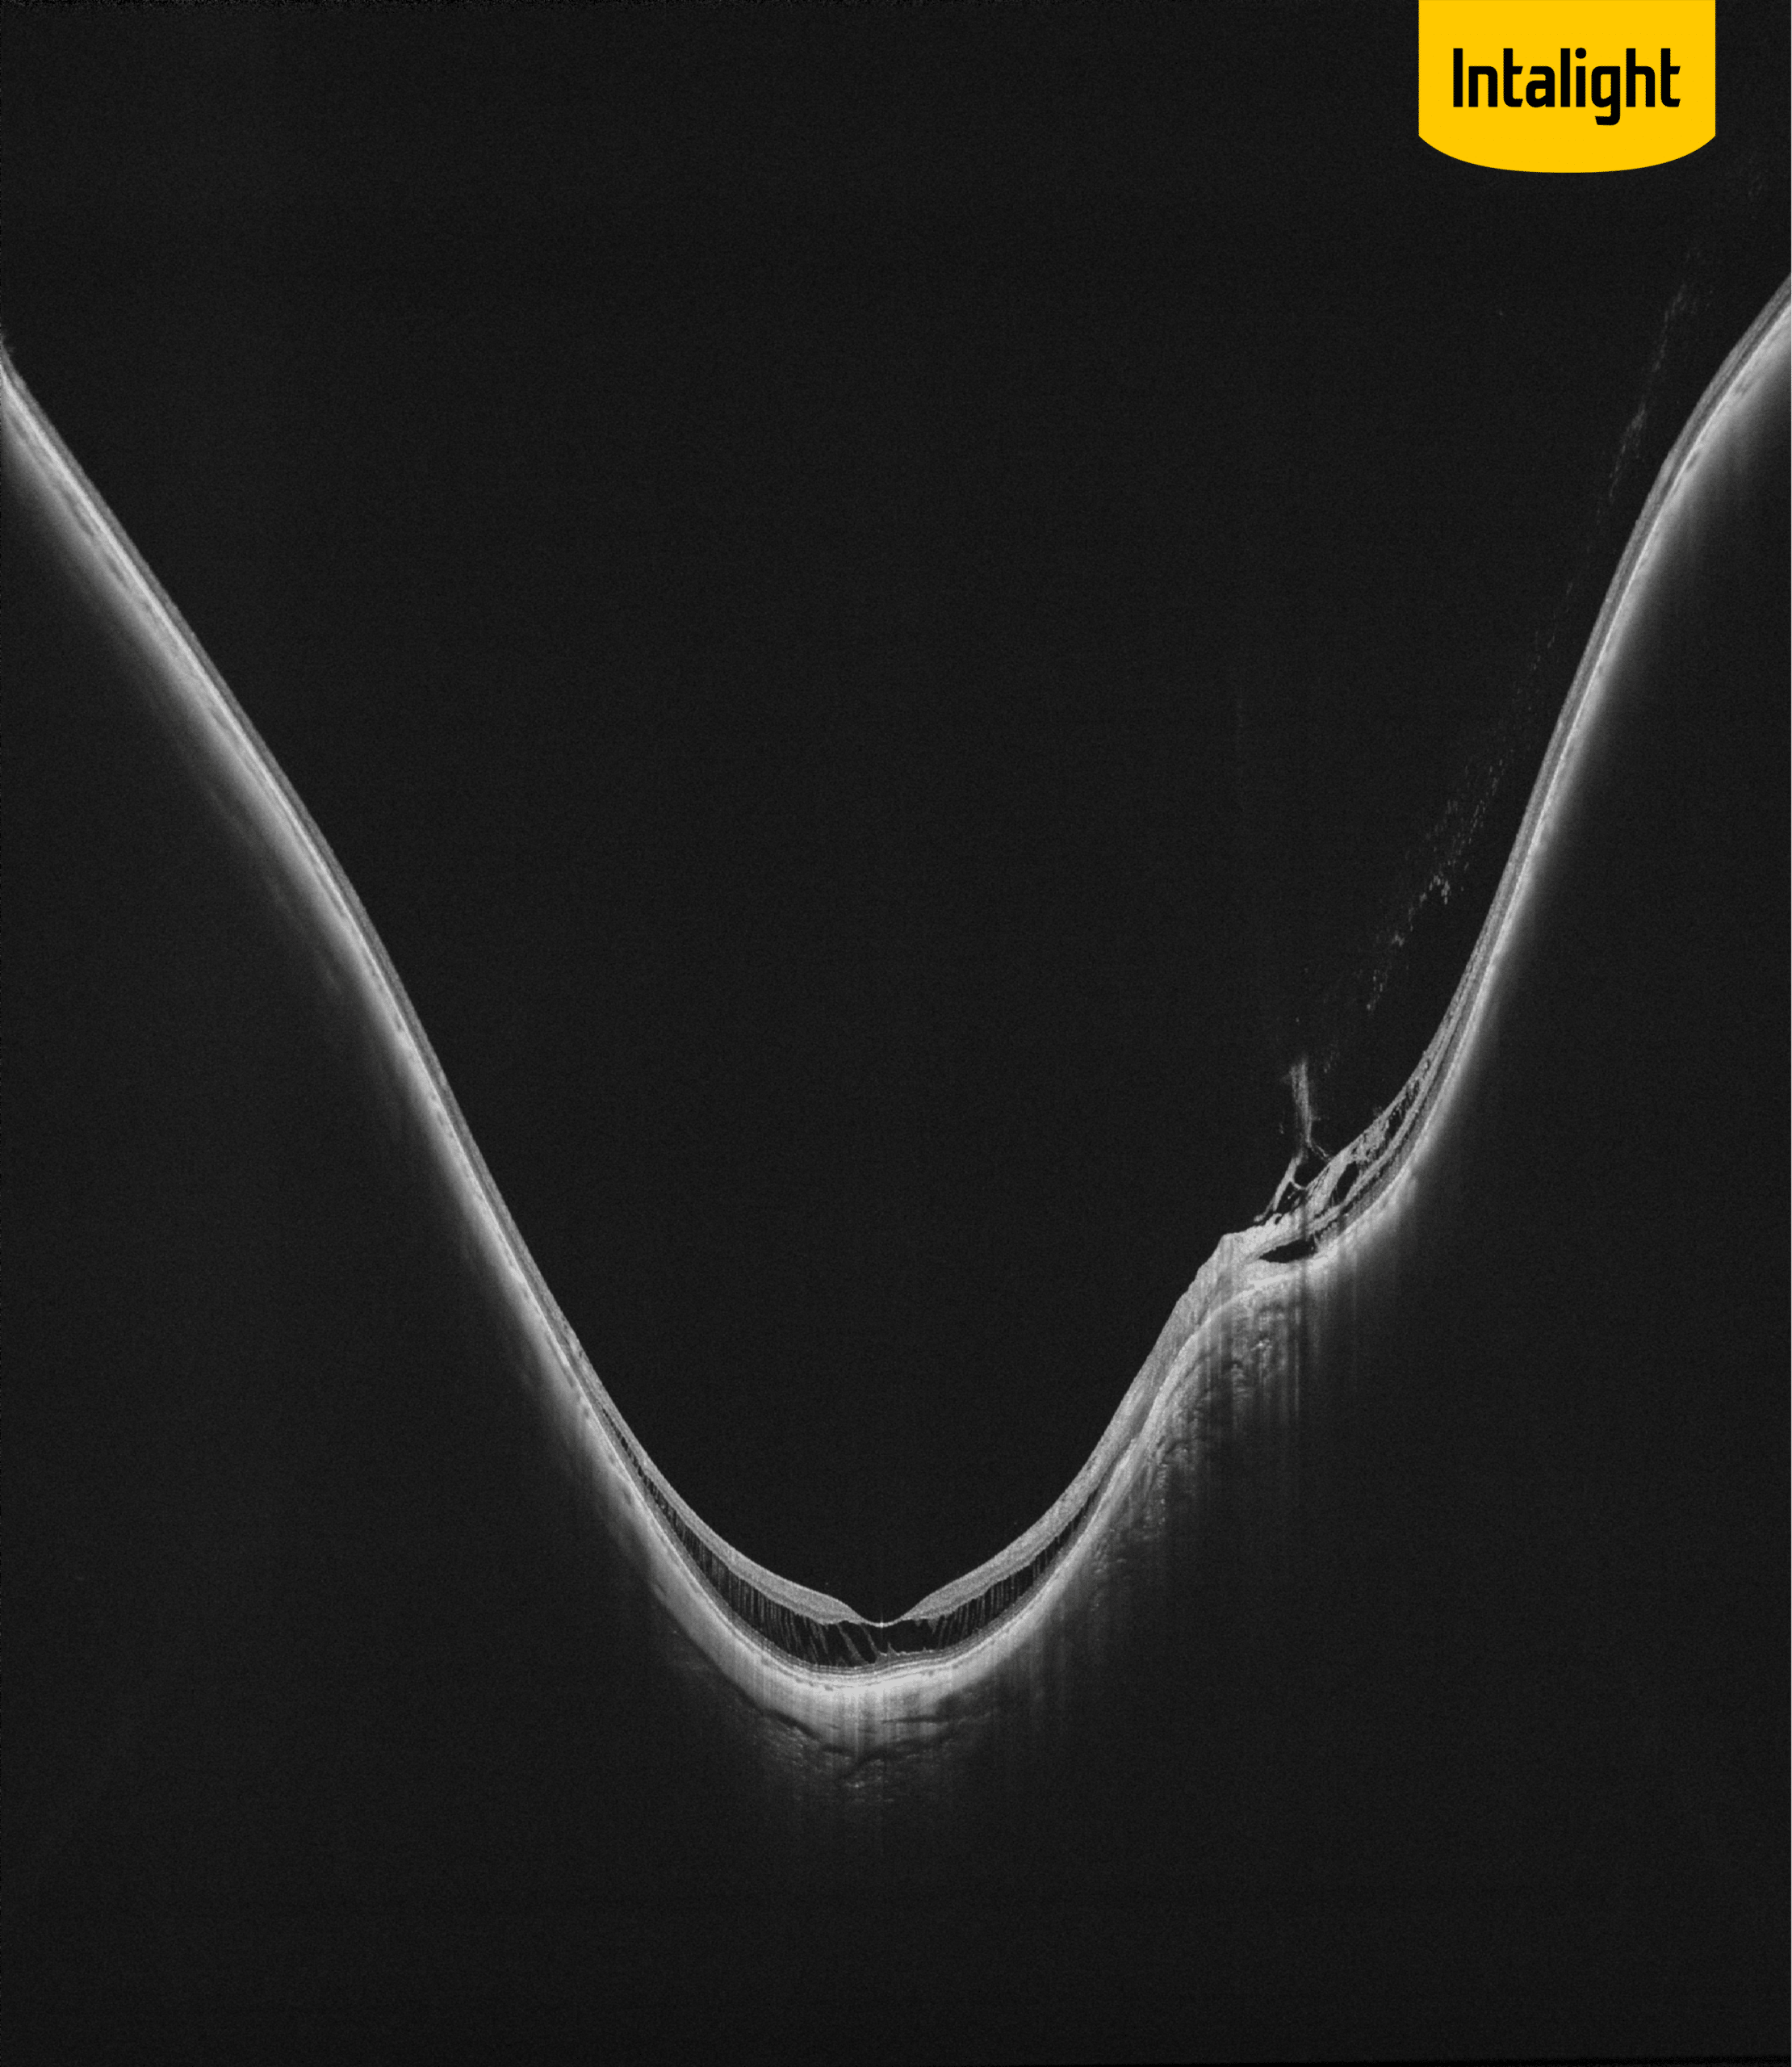

DREAM OCT : analyse grande profondeur du segment antérieur